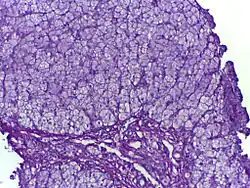

![]() | |

| Glycogen storage disease in hepatocytes | |

| Symptoms | Biopsy shows either abnormal accumulation or deficit of glycogen |